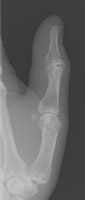

- Click on the image for a larger versionDLateral radiograph of the fourth PIP. This shows dislocation of this joint.